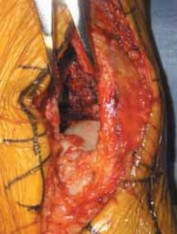

A careful vascular examination is important in evaluating patients with high-energy pilon injuries, as arterial compromise appears to be more common than previously appreciated (which may help explain the relatively high complication rates seen with early ORIF).

Findings of vascular compromise may be subtle (such as a one-vessel injury [eg, anterior tibial artery]) owing to collateral or retrograde flow patterns. Arterial compression testing (Allen test) about the ankle or the addition of angiography to CT may be a useful tool to further evaluate the local vasculature.